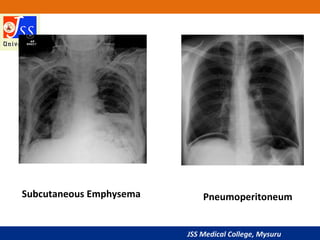

Soft Tissue

• Thick soft tissue due to obesity may obscure some underlying

structures such as lung markings

• Breast tissue may obscure the costophrenic angles

• Lucencies within soft tissue may represent gas (as observed with

subcutaneous air)

•Supraclavicular fossae

(enlarged nodes)

•Lateral chest wall

(surgical emphysema)

•Under diaphragm

(pneumoperitoneum)

Soft Tissues

Subcutaneous Emphysema Pneumoperitoneum